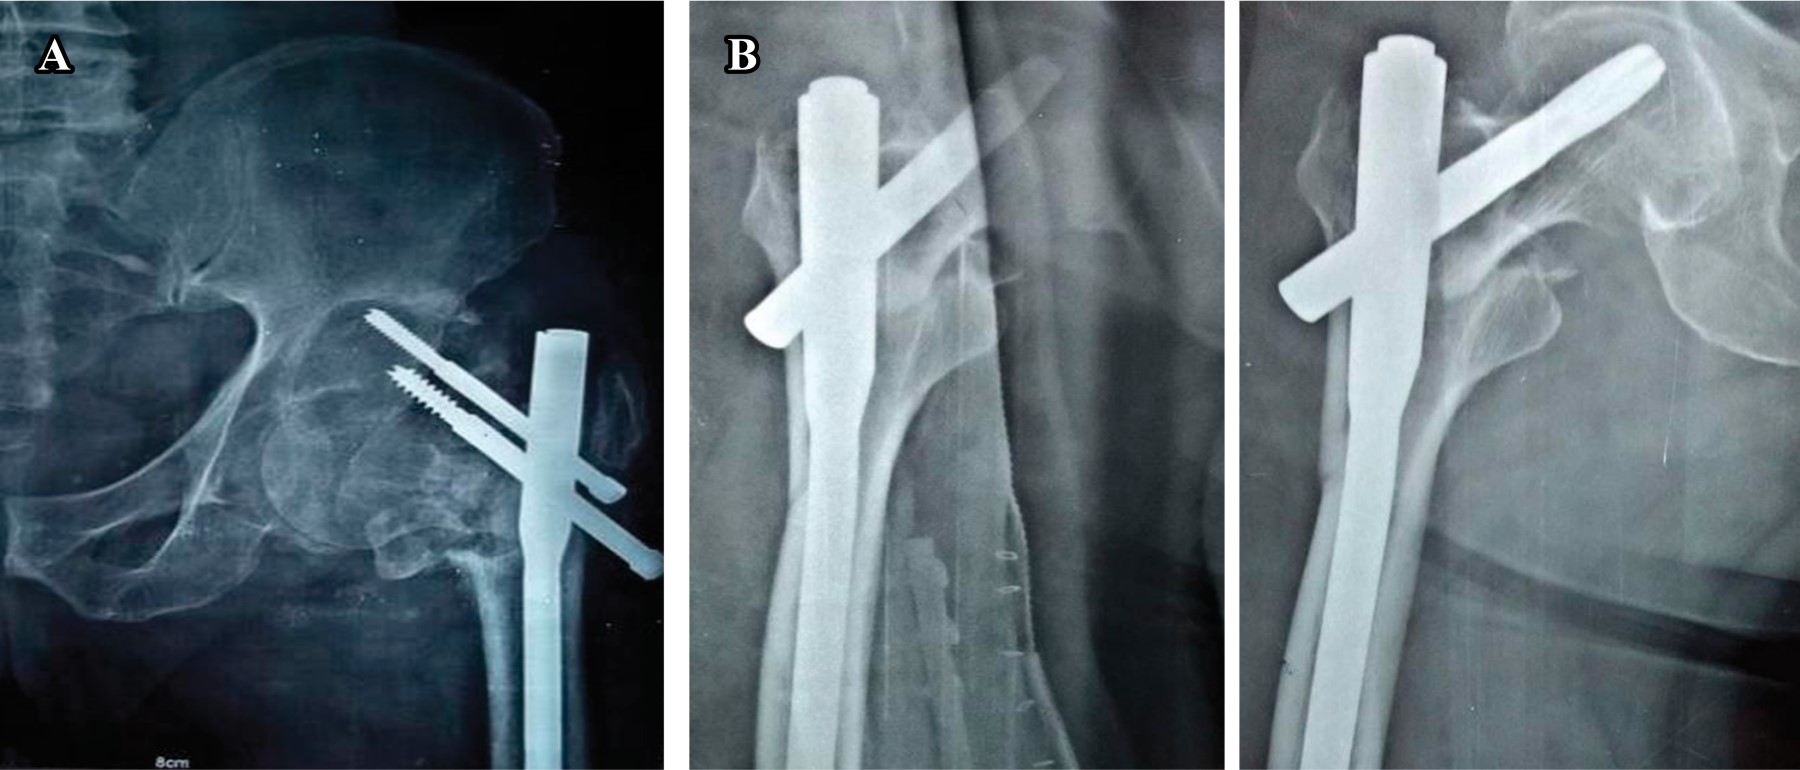

Implant related complications like screw back out (Figure 1), guide wire breakage (Figures 2 and 3), Z effect (Figure 4), TAD outliers (Figure 5) were more in PFN group whereas lateral screw protrusion, locking mechanism failure and barrel disengagement was more in PFNA2 group as shown in Figures 6, 7, 8 and 9. Neck shaft valgus outliers are more common in PFN group (Figure 10).

Implant-related complications, such as screw back-out, guidewire breakage, and proximal protrusion, were more pronounced in the PFN group, whereas lateral screw protrusion and medial migration were notable in the PFNA2 group.24 Lateral screw protrusion was observed in four patients in the PFNA2 group and one patient in the PFN group at the final follow-up in our study. Hu et al suggested a morphological mismatch in the Asian population between the proximal fragment of PFNA2 and the greater trochanter, leading to post-operative lateral trochanter pain.24